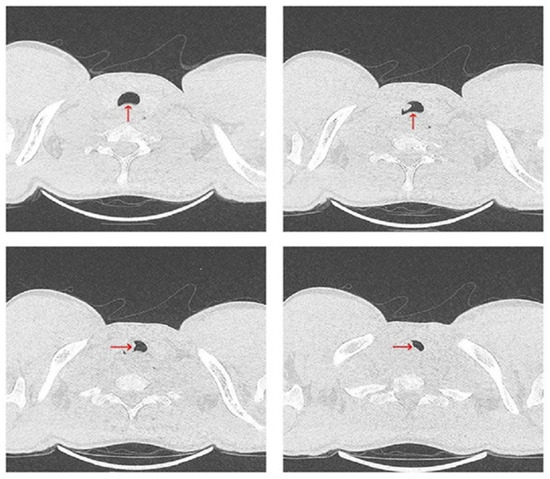

2. Case Report